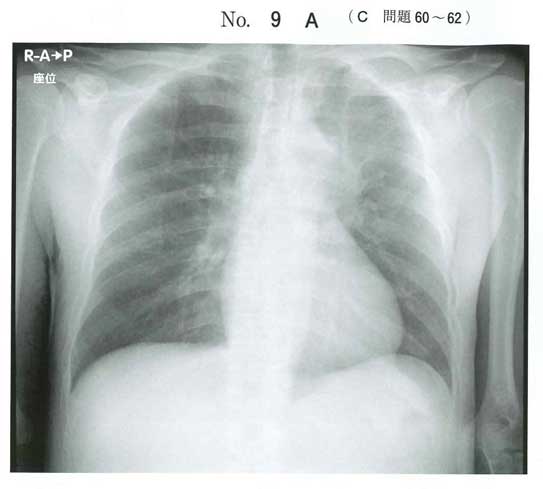

肺癌がありそうなのでSIADHかと思いますが、

腹部CTは左の副腎に腺腫がありそうですが、肺癌転移の可能性も考慮しろってことですかね?

食思不振、倦怠感、低血圧、Na118、好酸球増多21%から副腎不全ぽいデータです。eCTで左副腎腫瘍ありそうです。左縦隔リンパ節腫脹とあわせると肺癌の副腎転移に伴う副腎不全でしょうか。ACTHとコルチゾールは必須ですが、SIADHの除外のためにレニンアルドステロンも提出してもいい気がします。(あとは副腎腫瘍の鑑別としてPAは上がるのでPAの除外のために)。治療はハイドロコートン点滴かと思います。